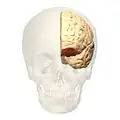

Поле Бродмана 11 в мозге человека

Поле Бродмана 11, или BA11, является частью лобной коры в мозге человека, орбитофронтальной коры, которая покрывает медиальную часть вентральной поверхности лобной доли.

Префронтальное Поле Бродмана 11-1909 является структурным подразделением лобной доли человека, что определено на основе цитоархитектоники.

Поле 11 представляет большинство орбитальных извилин, прямую извилину и наиболее ростральную часть верхней лобной извилины. Она граничит медиально с нижней ростральной бороздой и латерально с фронтомаргинальной бороздой. Цитоархитектонично граничит рострально и латерально с полем 10, полем 47, и полем 45; на медиальной поверхности граничит дорсально с полем 12 и каудально с полем 25. Известно, что префронтальное поле 11 образца 1909 года было больше; оно включало нынешнюю часть поля 12.[4]

Изображения

Анимация.

Анимация. вид спереди.

вид спереди. Боковой вид.

Боковой вид.